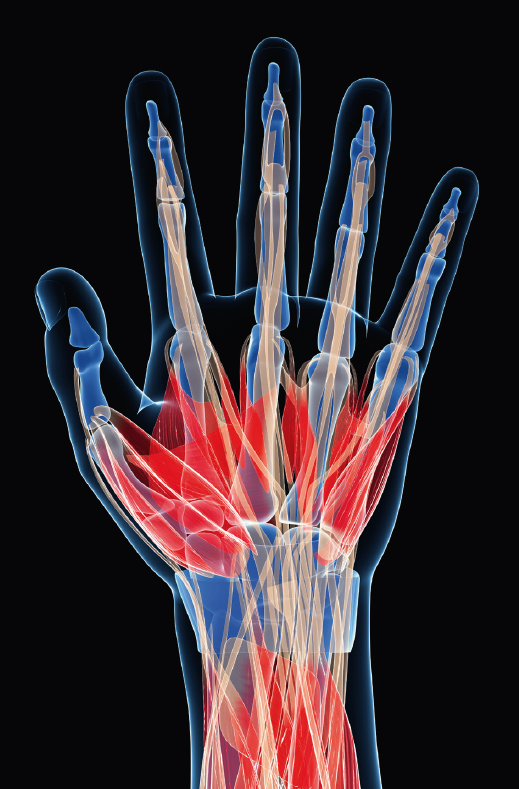

Each hand and wrist is made up of 27 bones. The finger bones or phalanges comprise of 14 bones – 2 in the thumb and 3 in each of the other four fingers. We, humans, have opposable thumbs which allow up to grasp objects. There are 5 bones in the palm called metacarpal bones. The hand is attached to the forearm by a joint called the wrist or carpus. The wrist joint is a complex system of 8 small bones known as the carpal bones linked by ligaments. The wrist acts as a type of pivot joint moving in relation to the forearm bones, the radius and ulna. It allows up (extension) and down (flexion) and side-to-side movement of the hand.